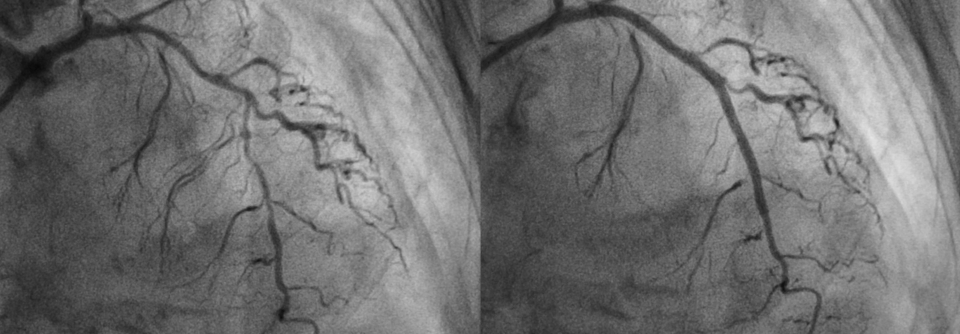

Über die optimale Therapie von Patienten mit stabiler Angina pectoris gehen die Meinungen auseinander. Hinsichtlich der Prognose schneiden perkutane Koronarintervention und Bypass nicht besser ab als eine medikamentöse Strategie. Zwei Herzspezialisten fassen das derzeitige Wissen zur Behandlung zusammen.

Knapp 40 000 Bypass-Operationen und mehr als 300 000 perkutane Koronarinterventionen (PCI) werden in Deutschland alljährlich durchgeführt, so die Daten von 2016. Ob all diese Eingriffe gerechtfertigt sind oder eine rein medikamentöse Therapie zu ähnlichen Ergebnissen führen würde, ist umstritten.

Nach der klassischen Vorstellung von der koronaren Herzkrankheit (KHK) verhindert eine epikardiale Stenose vor allem unter Belastung eine adäquate Zunahme des koronaren Blutflusses und führt so zur Angina pectoris. Demnach müssten revaskularisierende Eingriffe (PCI, Bypass) ein erneutes Auftreten der Schmerzen verhindern. Doch ganz so einfach ist es nicht: Viele Patienten leiden auch nach der PCI…